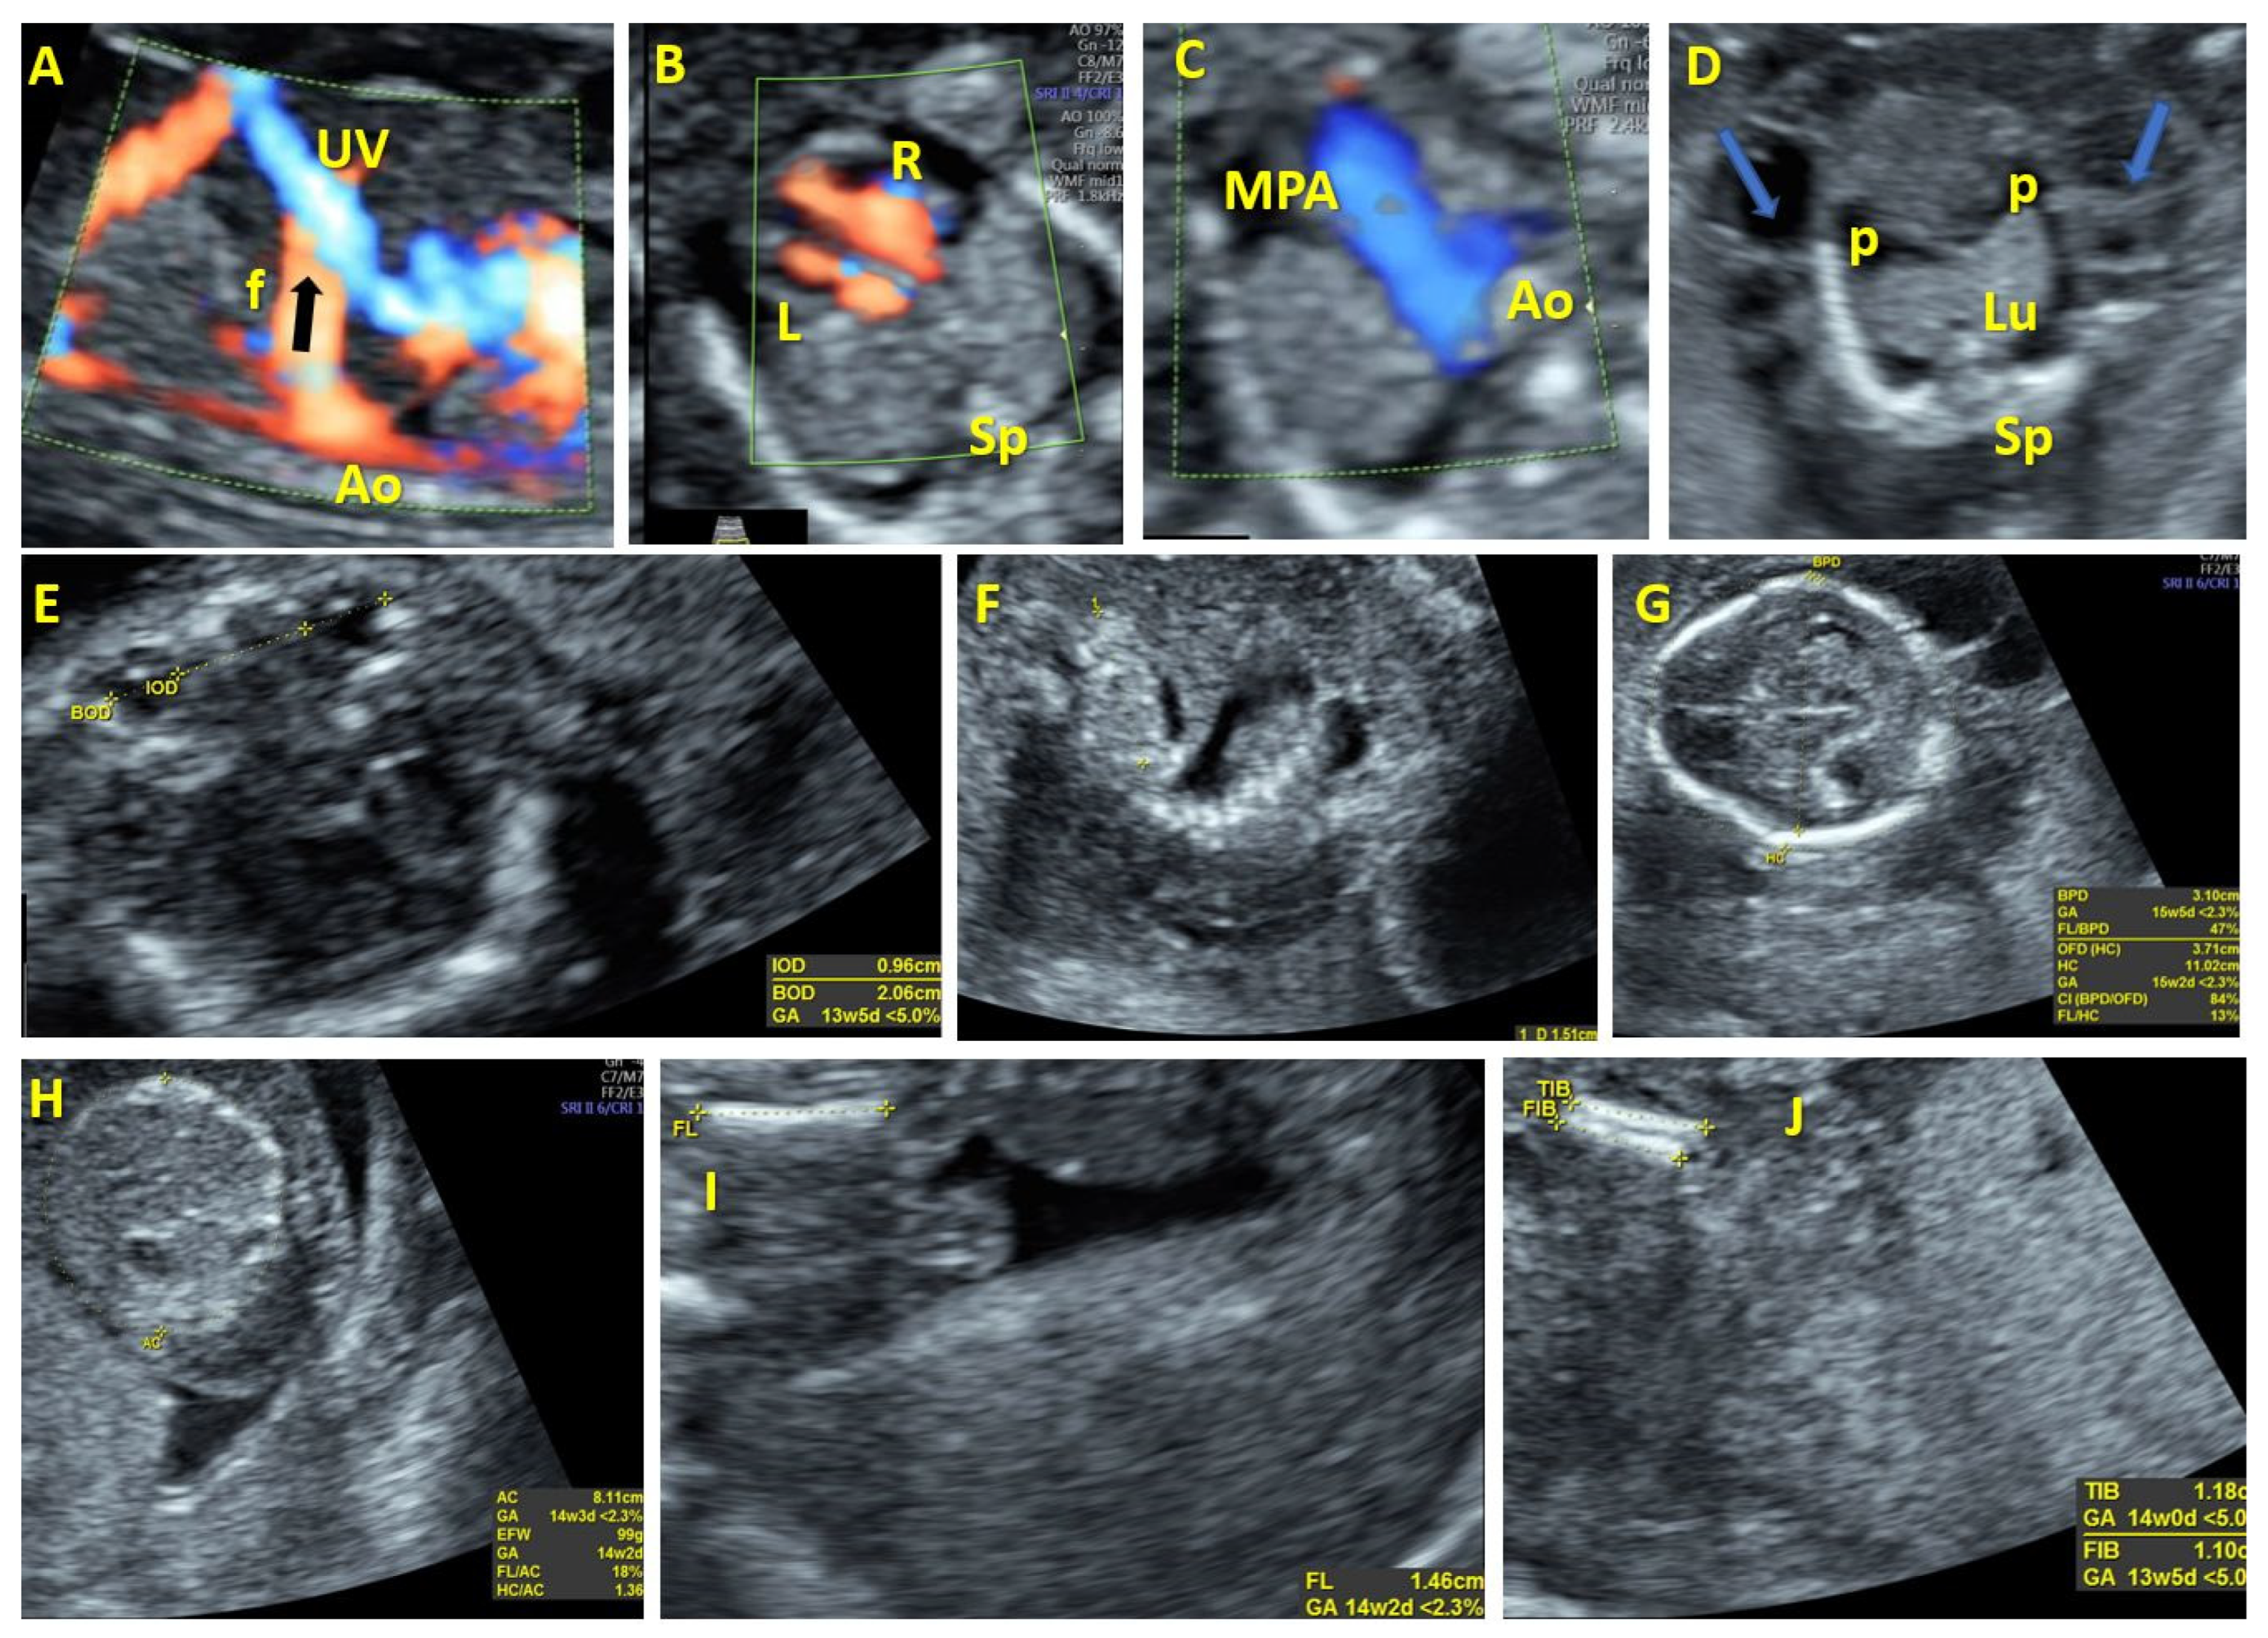

| 1 | 17 | Atypical vessel | Dilation of right heart chambers, early IUGR, hypotelorism, dysplastic kidneys, hydrops fetalis | Aorta-umbilical vein | Arterial flow | Follow-up | Fetal distress | 45X | Not applicable | Abortion at 19 WG |

| 2 | 19 | Intrahepatic arteriovenous complex malformation | Vermian malrotation, partial agenesis of the corpus callosum, frontal bossing, low nasal bridge, dilation of right heart chambers | Aorta-umbilical vein | Arterial flow | Follow-up | Fetal distress | Mosaic trisomy 17 | Not applicable | Abortion at 22 WG |

| 3 | 22 | Atypical vessel | Hydrocephalus, corpus callosum hypoplasia | Aorta-umbilical vein | Arterial flow | Follow-up | Stationary | Normal | Not applicable | Abortion at 23 WG |

| 4 | 13 | Atypical vessel | Cystic hygroma PVSA | Aorta-umbilical vein | Arterial flow | Follow-up | Fetal distress | Not performed | Not applicable | Abortion |

| 5 | 13 | Atypical vessel | Bilateral radius agenesis | Aorto-hepatic vein | Not evaluated | Follow-up | Stationary | T18 | Not applicable | Abortion |

| 6 | 13 | Atypical vessel | Megacystis, hand and foot malposition, skeletal malformations, hygroma, hemivertebra, VSD absent CSP | Aorta-umbilical vein | Not evaluated | Follow-up | Fetal distress | Not performed | Not applicable | Abortion |

| 7 | 13 Twin pregnancy | Atypical vessel | Absent | Aorta-umbilical vein | Arterial flow | Follow-up | Fetal distress | T21 | Not applicable | IUD of the affected fetus |

| 8 | 30 | Dilated vascular channels within the liver | Dilation of right heart chambers | Aorto-hepatic vein | Arterial flow | Follow-up | Stationary | Normal | Embolization of the fistulous tract | Death due to cardiac failure |